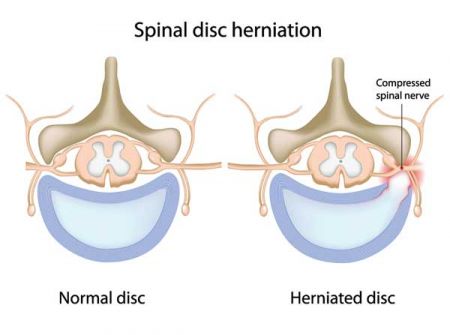

If disc material herniates, or squeezes out, this can put pressure on the spinal cord or spinal nerves. This can cause severe pain in the path of the nerve being pinched. Pressure against the nerve root from a herniated disc can cause numbness and weakness along the nerve. When the nerve root is inflamed, the added pressure may also cause vague, deep pain and/or cause sharp, shooting pain to radiate along the pathway of the nerve. There is also evidence that the nucleus pulposus material is quite acidic and causes a chemical irritation of the nerve roots. The consistency of a disc depends upon whether it is the outer tough annular portion or the central soft nuclear portion. In lay terms many compare the consistency of a disc herniation to that of lobster or crab meat.

Specifically, a disc fragment in the neck that pinches a nerve to the arm would cause arm pain, whereas in the low back a piece of disc that breaks off and pinches a lower extremity nerve would cause leg pain. This can also happen in the mid-back and cause pain that wraps around the trunk. Depending upon which nerve is pinched different pain patterns may arise. Classic sciatica, which is pain down the back of the thigh and calf, is usually caused by a herniation at one of the bottom two levels of the spinal canal pinching the L5 and/or S1 nerve and producing pain in that pattern.

The symptoms of a herniated disc may not include a wide array of pain. The symptoms come from increased pressure and irritation of the nerves. Many people may not have neck or back pain with a herniated disc. Symptoms of a herniated disc usually include pain that travels into one or both arms or legs, numbness or tingling in areas of extremities, muscle weakness, and loss of the reflexes in extremities. Where these symptoms occur depends on where the herniation is located. The location of the symptoms helps determine the diagnosis as nerves usually travel in specific patterns.

If disc material herniates, or squeezes out, this can put pressure on the spinal cord or spinal nerves. This can cause severe pain in the path of the nerve being pinched. Pressure against the nerve root from a herniated disc can cause numbness and weakness along the nerve. When the nerve root is inflamed, the added pressure may also cause vague, deep pain and/or cause sharp, shooting pain to radiate along the pathway of the nerve. There is also evidence that the nucleus pulposus material is quite acidic and causes a chemical irritation of the nerve roots. The consistency of a disc depends upon whether it is the outer tough annular portion or the central soft nuclear portion. In lay terms many compare the consistency of a disc herniation to that of lobster or crab meat.

Specifically, a disc fragment in the neck that pinches a nerve to the arm would cause arm pain, whereas in the low back a piece of disc that breaks off and pinches a lower extremity nerve would cause leg pain. This can also happen in the mid-back and cause pain that wraps around the trunk. Depending upon which nerve is pinched different pain patterns may arise. Classic sciatica, which is pain down the back of the thigh and calf, is usually caused by a herniation at one of the bottom two levels of the spinal canal pinching the L5 and/or S1 nerve and producing pain in that pattern.

The symptoms of a herniated disc may not include a wide array of pain. The symptoms come from increased pressure and irritation of the nerves. Many people may not have neck or back pain with a herniated disc. Symptoms of a herniated disc usually include pain that travels into one or both arms or legs, numbness or tingling in areas of extremities, muscle weakness, and loss of the reflexes in extremities. Where these symptoms occur depends on where the herniation is located. The location of the symptoms helps determine the diagnosis as nerves usually travel in specific patterns.